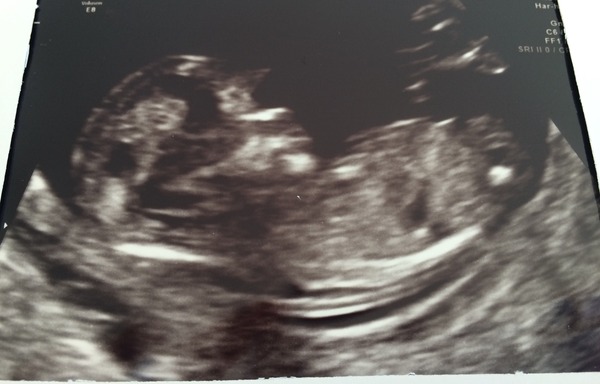

So today was the day, had my all in one booking, scan and bloods done.

I've been put forward to 13 weeks today. Which I thought might happen as I was 12+3 and this baby implanted very early so not surprised I've dropped half a week.

Everything was fine, I got a 2mm nuchal measurement which having looked online seems really good for 13 weeks. But I haven't had the official ratio back yet.

Fab news Sairie! Mine was 2mm too. Lovely little face :)